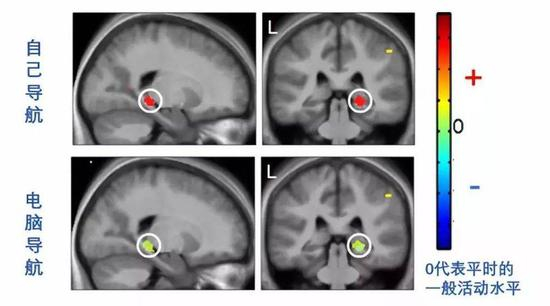

实验地点仍是伦敦市中心。实验参与者在熟悉了一系列街区之后,在导航测试的一些回合自己判断该往哪走,在另一些回合选择电脑指定的方向。

当参与者自己判断怎么走时,海马处于激活状态,而依赖电脑做决策时,海马不再活跃。

也就是说,依赖外挂的设备之后,海马原有的导航功能被闲置了。